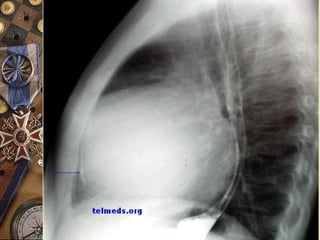

ELECTROCARDIOGRAMAELECTROCARDIOGRAMA

Alternancia eléctrica

 Signo de la

cantimplora